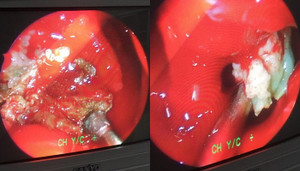

Các bác sỹ Bệnh viện Việt Nam – Thụy Điển vừa phẫu thuật thành công một ca lồng ruột hy hữu ở người lớn, do khối u ruột non gây ra.